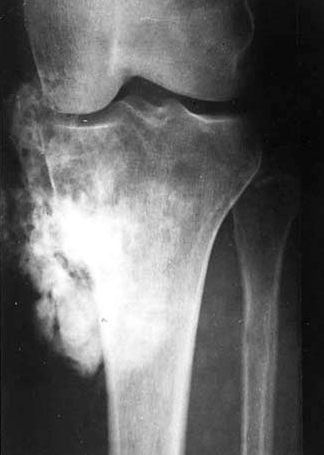

Location of osteosarcoma

Metaphysis of long bones

• Femur, tibia, humerus (56%); flat

Describe what to expect in Xray of osteosarcoma

Infiltrative tumor… extends to soft tissues. Has malignant cells producing osteoid

Osteosarcoma